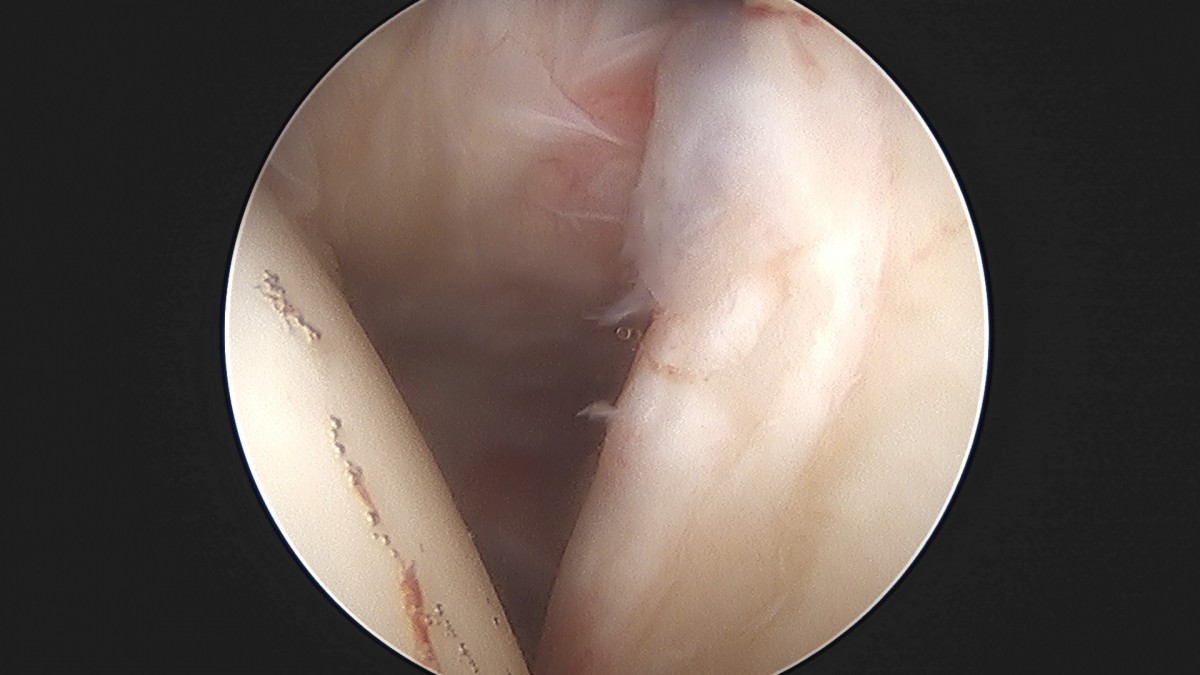

정지영원장님 어깨 관절낭 이완술 이상O 환자

작성자 최고관리자 댓글 0건 조회 743회 작성일 25-09-16 16:58